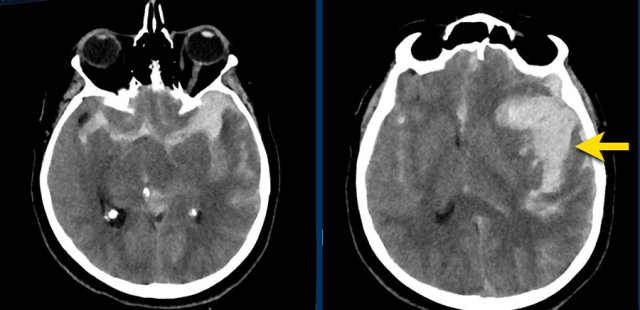

Right lower image is venous infarction due to sinus thrombosis (yellow arrows) Right lower image is venous infarction due to sinus thrombosis (yellow arrows)

This patient presented with a subarachnoidal haemorrhage due to an aneurysm in the anterior communicating artery.

There is also an intraparenchymal heamatoma in the right gyrus rectus (arrow).

NCCT shows bilateral subarachnoid hemorrhage  and a parenchymal hemorrhage (yellow arrow).

CTA show at the location of the parenchymal hemorrhage a flow related aneurysm of the anterior communicans artery, which was considered the cause of the SAH.

Notice the hemorrhage next to the aneurysm (circle).